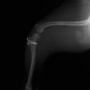

膝蓋骨脱臼は膝関節における膝蓋骨の内外側の脱臼と定義されるが、時として単純な内外の脱臼ではなく、膝蓋骨が大きく前方に浮き上がるように脱臼する場合がある。特にトイプードルやポメラニアンといった犬種に多く認められる。

内側脱臼に加えて前方への浮き上がりを矯正する為に、従来より脛骨粗面転移により膝蓋靭帯を外方と下方に引っ張り、固定する方法を選択する。膝蓋骨の前方への浮き上がりが軽度の場合は、従来法ではなく関節包の縫縮で対応していた。しかし、一部の症例で膝蓋骨の動きが悪くなり伸展機構が円滑に機能せずロボット様歩行になるケースがあった。

その為、膝蓋靭帯自体を縫縮する方法を採用した。この方法により、膝関節の伸展機構を妨げず膝蓋骨の軽度の浮きを矯正することが可能となった。

本症例の経過は良好である